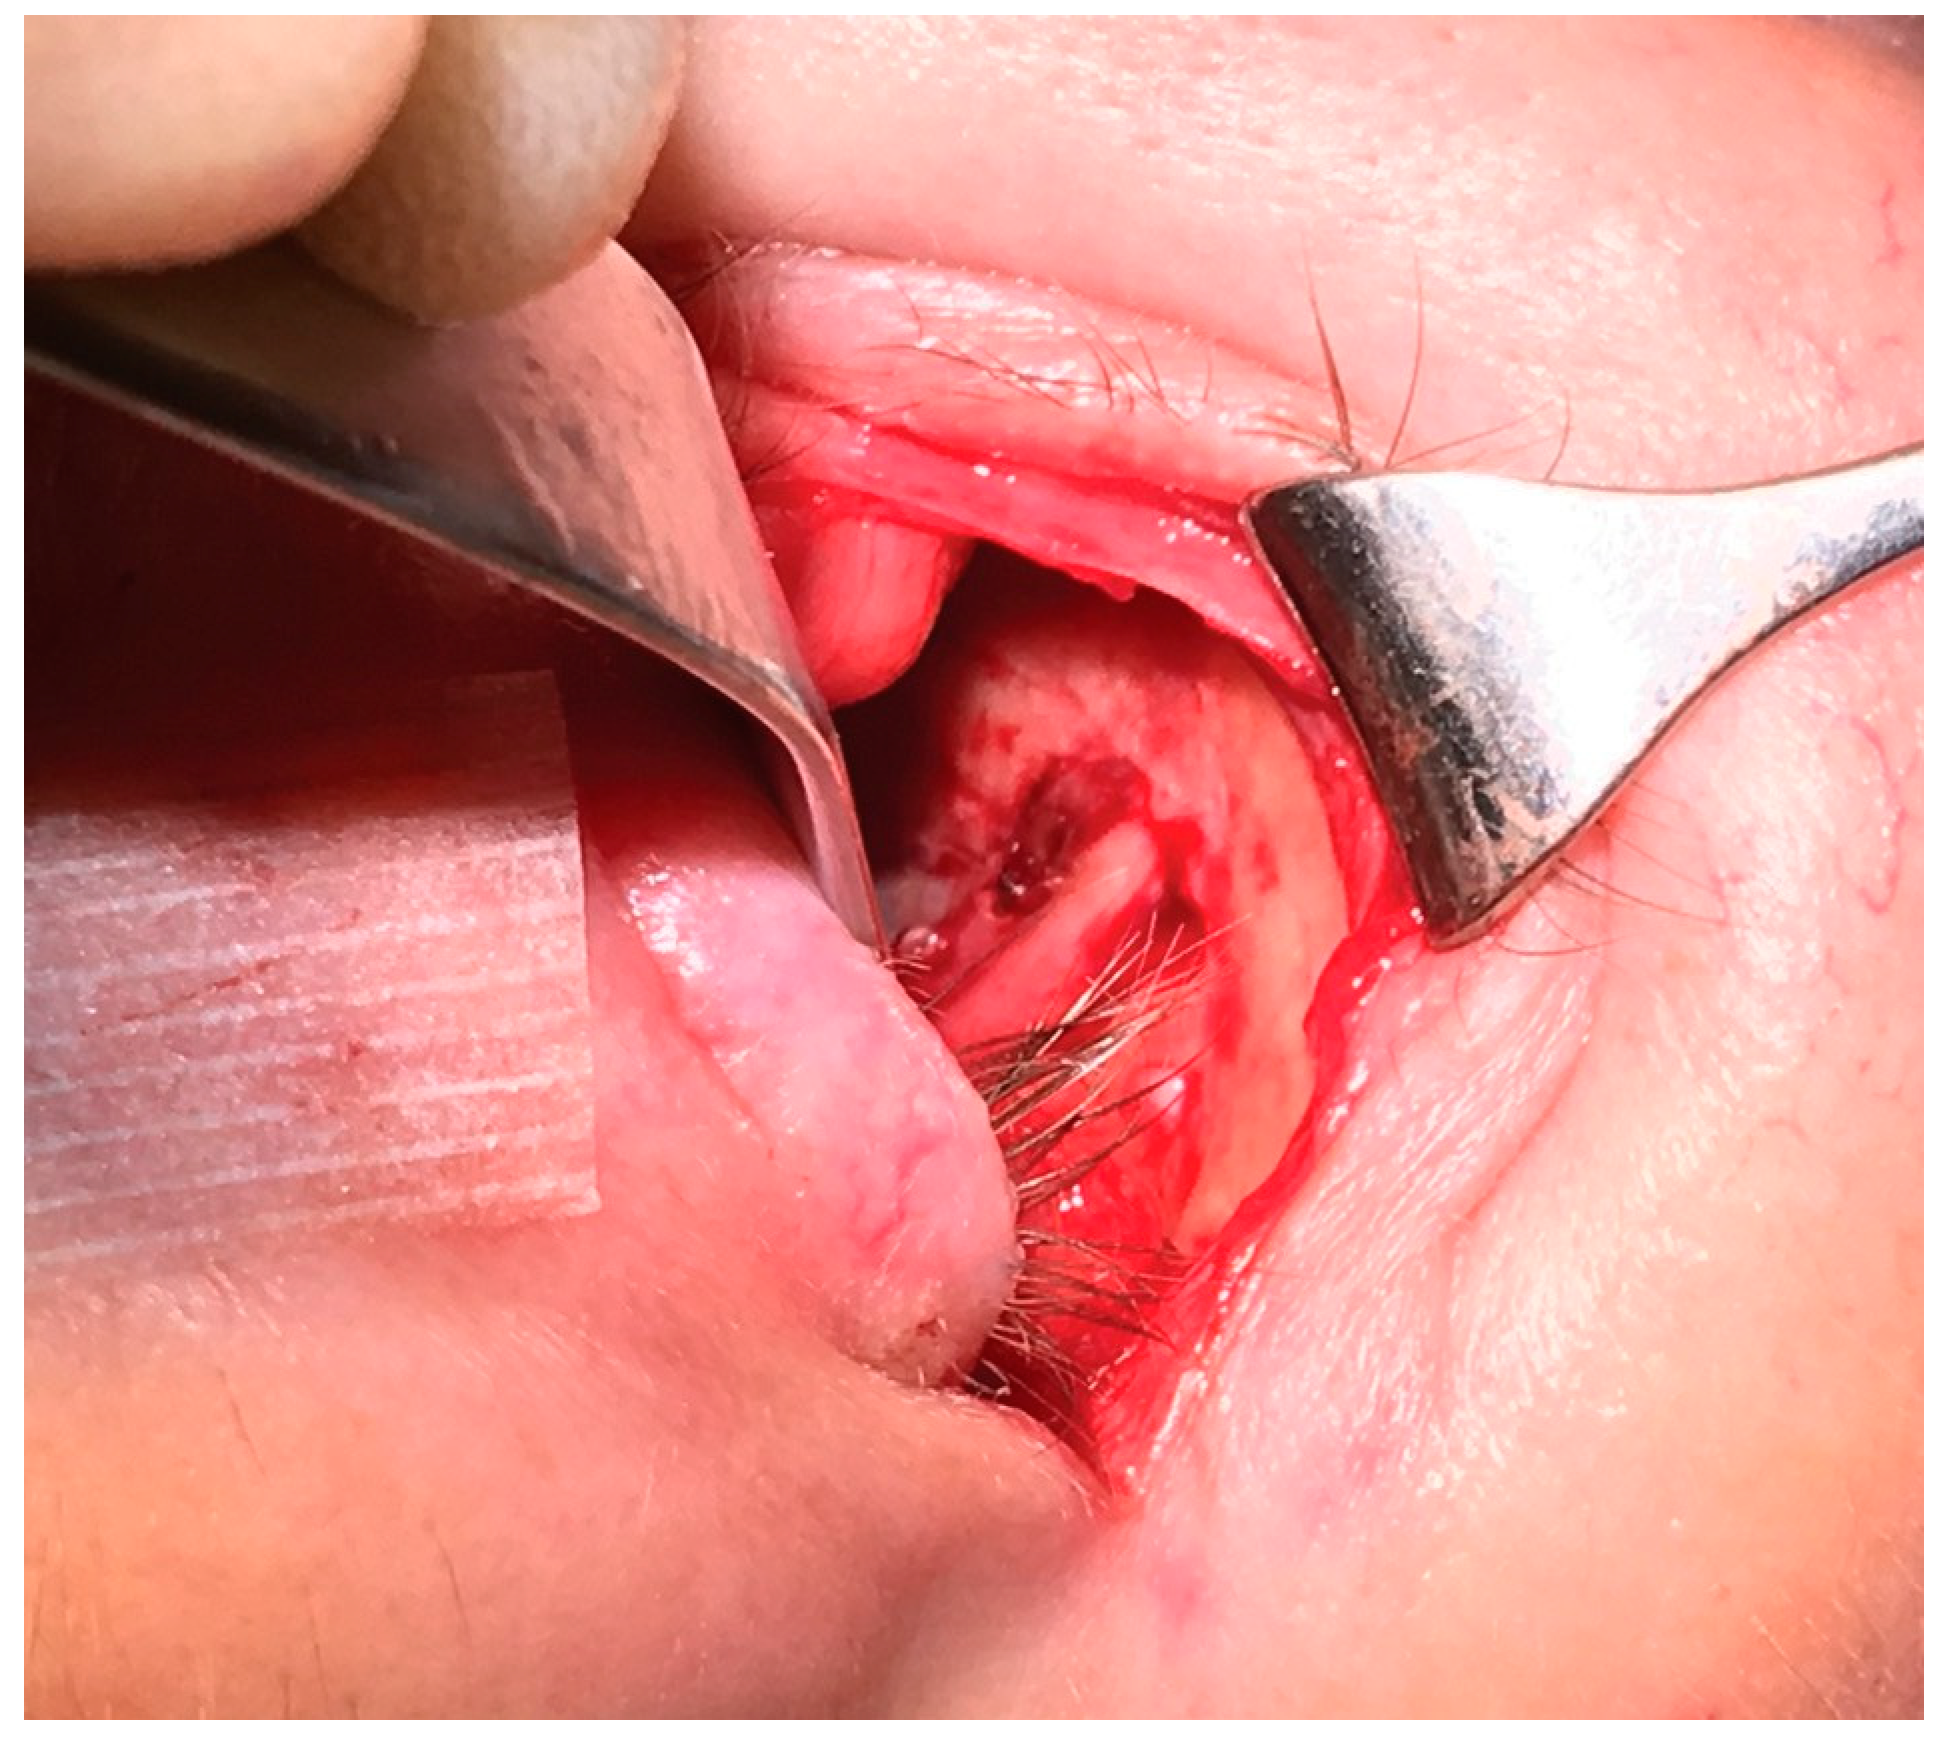

Case 1